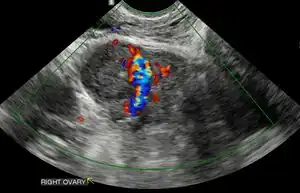

Obstetric ultrasonography may also be used to detect and diagnose pregnancy. It is very common to have a positive at home urine pregnancy test before an ultrasound. Both abdominal and vaginal ultrasound may be used, but vaginal ultrasound allows for earlier visualization of the pregnancy. With obstetric ultrasonography the gestational sac (intrauterine fluid collection) can be visualized at 4.5 to 5 weeks gestation, the yolk sac at 5 to 6 weeks gestation, and fetal pole at 5.5 to 6 weeks gestation. Ultrasound is used to diagnose multiple gestation.[3][19]

-

Ultrasound: early pregnancy -

Ultrasound: failed early pregnancy

Ultrasound is also a common tool for determining viability and location of a pregnancy. Serial ultrasound may be used to identify non-viable pregnancies, as pregnancies that do not grow in size or develop expected structural findings on repeated ultrasounds over a 1-2 week interval may be identified as abnormal.[34] Occasionally, a single ultrasound may be used to identify a pregnancy as non-viable; for example, an embryo that is greater than a certain size but that lacks a visible heart beat may be confidently determined to be not viable without the need for follow up ultrasound for confirmation.[34]